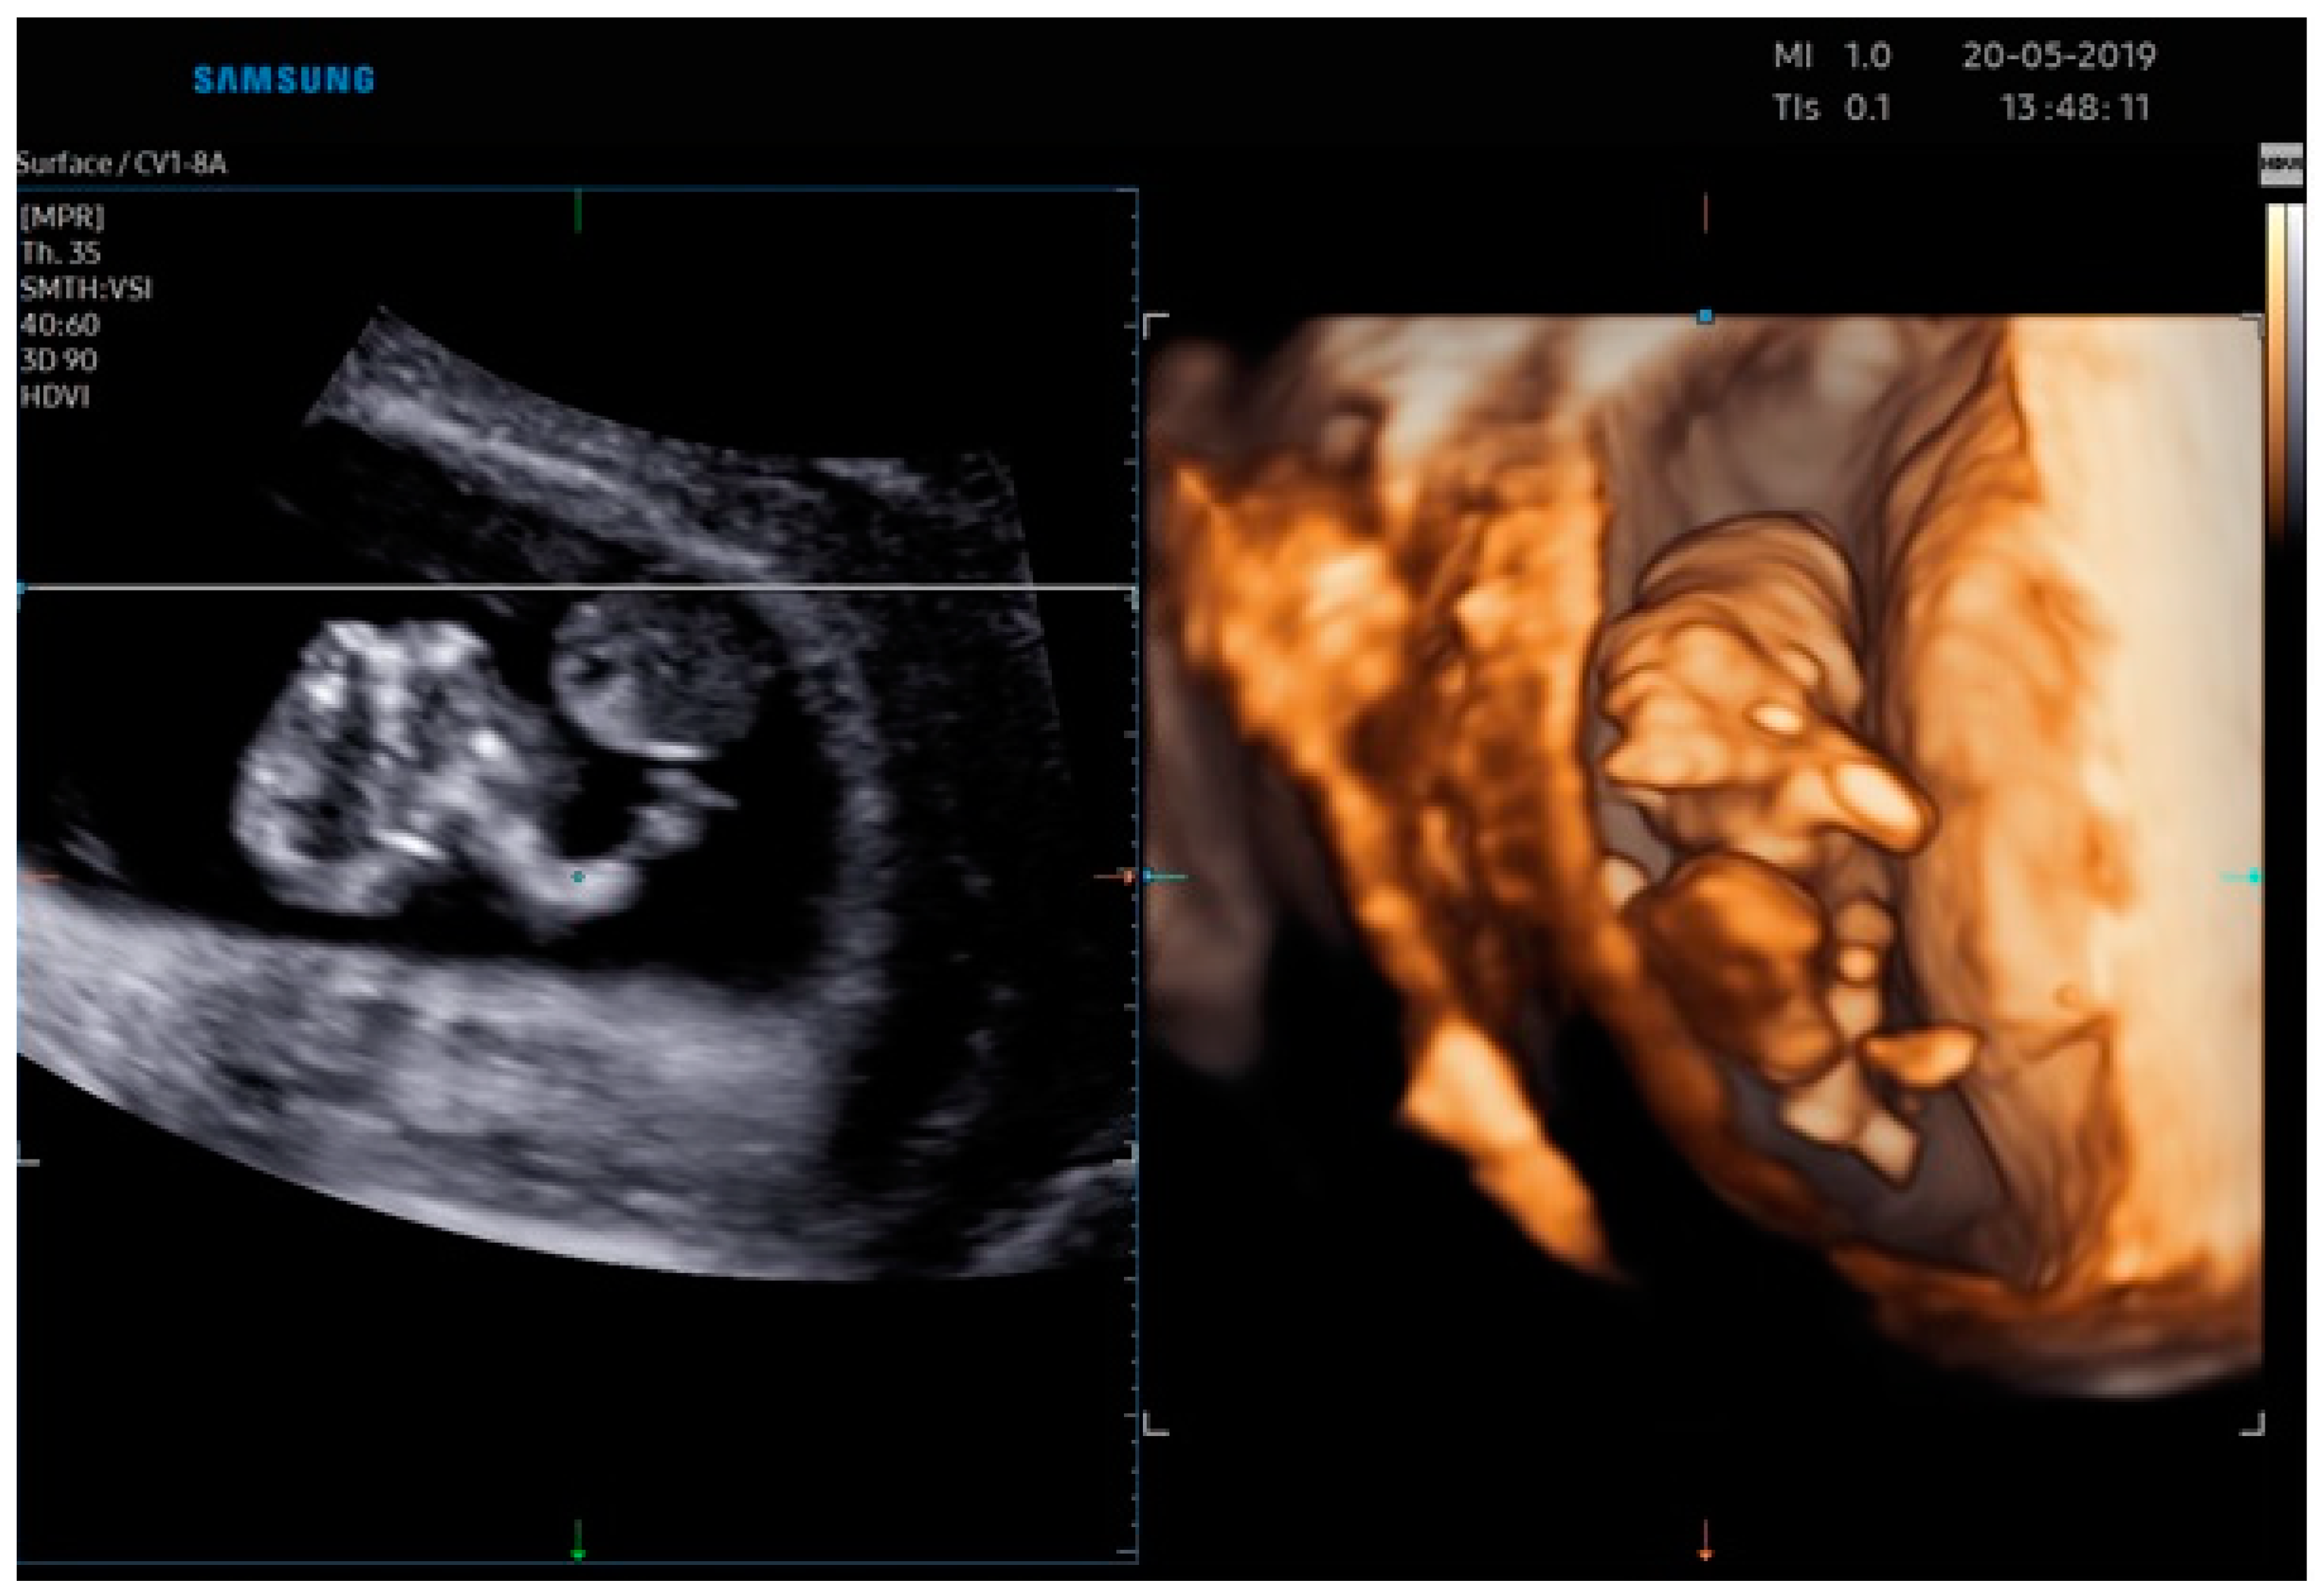

2.1. Case Report 1